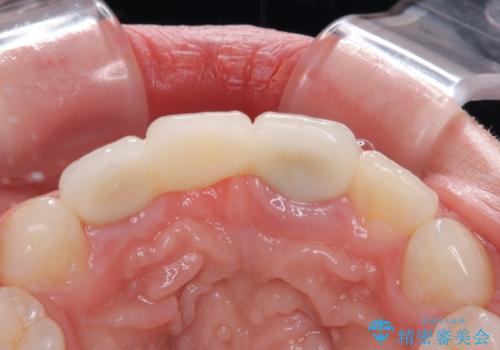

歯肉ラインを整えるために歯肉移植術を行うか悩んでいましたが、行わないという判断をされたため、やや不揃いの歯肉ラインとなりました。